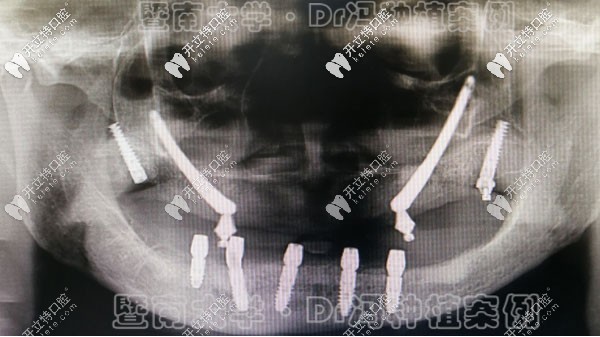

這位大姐姐的牙齒癥狀是:上頜發(fā)育不足,下頜發(fā)育過度,且下牙列擁擠,呈重度地包天面型。

她的正頜手術(shù)很順利,術(shù)后面型:地包天完全改善,恢復(fù)正常面型,牙列排齊,已經(jīng)進入精調(diào)咬合的階段,預(yù)計再有半年左右就可以下牙套了。